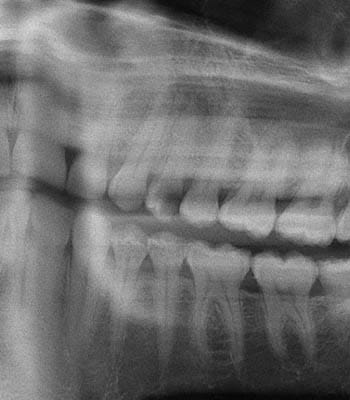

Dental implants are a titanium "root" which can be placed into the jawbone. Once integrated with your bone, the implant can be used to support a crown, a bridge, or secure a complete denture. Dental implants may be used to eliminate partial plates and dentures. The success rates for dental implants are extremely high which is due in part to the fact that root-form implants are made of a biocompatible material, titanium.